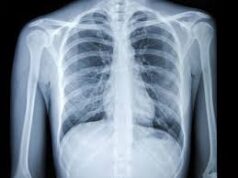

Over 1 lakh chest X-rays screened using AI in Goa; diagnosis time cut by...

Digital Goa, February, 3 - With the support of AstraZeneca and Qure.AI, over one lakh chest X-rays have been screened across Goa using artificial...